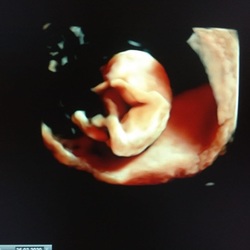

Hoi! Ik heb een hele zware vorm van hartritmestoornissen en slik daar normaliter 2x per dag 7.5mg procoralan voor. Nu heb ik ook weer gelukkig groen licht gehad en ben ik 10 weken zwanger. Eerst moest ik 6 weken gestopt zijn voor we 眉berhaupt zwanger mochten worden.

Ik heb de vorige zwangerschap ook tot 32 weken uit kunnen zingen dus dat is mijn eerste doel.. Ik mag helemaal de hele zwangerschap geen procoralan innemen helaas.